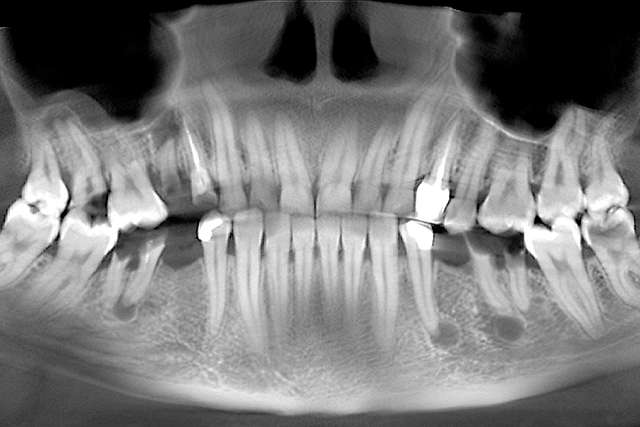

Dental implants are treatments designed for teeth that we can no longer save. Dental implants rely on the principle of osseointegration, or in other words, on the implant being integrated in the bone. For a long period of time, this was the main objective of the industry. Osseointegration, placing implants in relation to bone. Today , we know that osseointegration is extremely predictable and we focus on key elements that can make the difference in the quality of the end result.

Guided surgery, for one, facilitates an ideal pre-planned position, in relation to available bone, and even more important, in relation to the future implant supported crown. Guided surgery translates into increased precision, which means safer surgeries, reduced surgery time, and reduced trauma. Also the focus of these types of treatments is shifted towards tissue reconstruction, which on the long run, has a far greater impact esthetically and biologically. Tissue stability means implant longevity. This case is a relevant example for this type of approach towards implant dentistry.